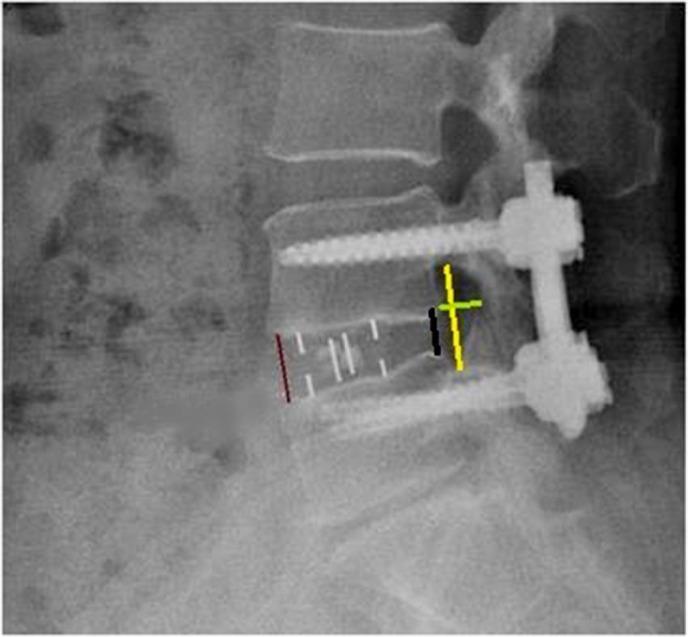

Based on the inclusion and exclusion criteria, the comparative analysis included consecutive patients with grade-1 degenerative spondylolisthesis who underwent oblique LIF (OLIF, n = 36) or minimally invasive transforaminal LIF (MI-TLIF, n = 45) at the Department of Spine Surgery, Beijing Jishuitan Hospital from January 2016 to August 2017. Patient satisfaction Japanese Orthopaedic Association score, visual analog scale (VAS) scores for back and leg pain, Oswestry disability index (ODI), radiographic outcomes including anterior/posterior disc heights (ADH/PDH), foraminal height (FH), foraminal width (FW), cage subsidence, cage retropulsion, and fusion rate were assessed during a 2-year follow-up. Continuous data are presented as mean ± standard deviation and were compared between groups using the independent sample t-test. Categorical data are presented as n (%) and were compared between groups using the Pearson chi-squared test or Fisher's exact test. Repetitive measurement and analysis of variance was employed in the analysis of ODI, back pain VAS score, and leg pain VAS score. Statistical significance was defined as p < 0.05.

The OLIF and MI-TLIF groups comprised 36 patients (age, 52.1 ± 7.2 years; 27 women) and 45 patients (age, 48.4 ± 14.4 years; 24 women), respectively. Satisfaction rates at 2 years post procedure exceeded 90% in both groups. The OLIF group had less intraoperative blood loss (140 ± 36 vs 233 ± 62 mL), lower back pain VAS score (2.42 ± 0.81 vs 3.38 ± 0.47), and ODI score (20.47 ± 2.53 vs 27.31 ± 3.71) at 3 months follow-up (with trends toward lower values at 2 years follow-up), but higher leg pain VAS scores at all postoperative time points than the MI-TLIF group (all p < 0.001). ADH, PDH, FD, and FW improved in both groups post-surgery. At the 2 year follow-up, the OLIF group had a higher rate of Bridwell grade-I fusion (100% vs 88.9%, p = 0.046) and lower incidences of cage subsidence (8.33% vs 46.67%, p < 0.001) and retropulsion (0% vs 6.67%, p = 0.046) than the MI-TLIF group.

OLIF 组和 MI-TLIF 组分别包括 36 例患者(年龄 52.1±7.2 岁,27 例女性)和 45 例患者(年龄 48.4±14.4 岁,24 例女性)。两组术后 2 年的满意度均超过 90%。OLIF 组术中出血量较少(140±36 比 233±62 mL),术后 3 个月时腰痛 VAS 评分(2.42±0.81 比 3.38±0.47)和 ODI 评分(20.47±2.53 比 27.31±3.71)较低(术后 2 年呈下降趋势),但术后各时间点腿痛 VAS 评分均高于 MI-TLIF 组(均 p<0.001)。两组术后 ADH、PDH、FD 和 FW 均得到改善。术后 2 年时,OLIF 组 Bridwell 分级融合率较高(100%比 88.9%,p=0.046),cage 下沉率较低(8.33%比 46.67%,p<0.001)和后移率较低(0%比 6.67%,p=0.046)。